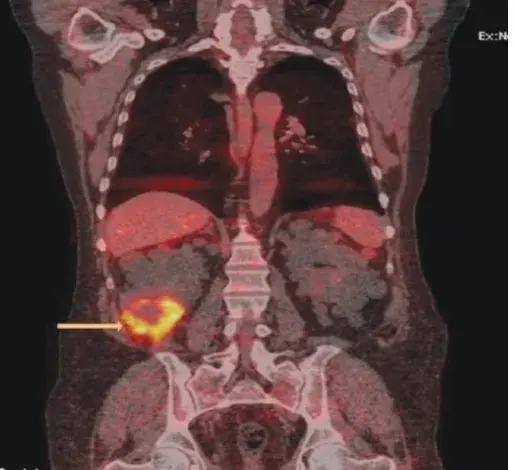

Após 04 após o último tratamento a paciente evoluiu com **novo** quadro de **edema nos membros inferiores**, **proteinúria** **de 8 g/dia** e **creatinina sérica de 1,27 mg/dl** (TFGe 37,5 ml/min/1,73m²), foi realizada uma nova biópsia renal (figura abaixo).

Esses achados foram diagnósticos de **nefropatia diabética sobreposta a lesões crônicas de nefrite lúpica**.